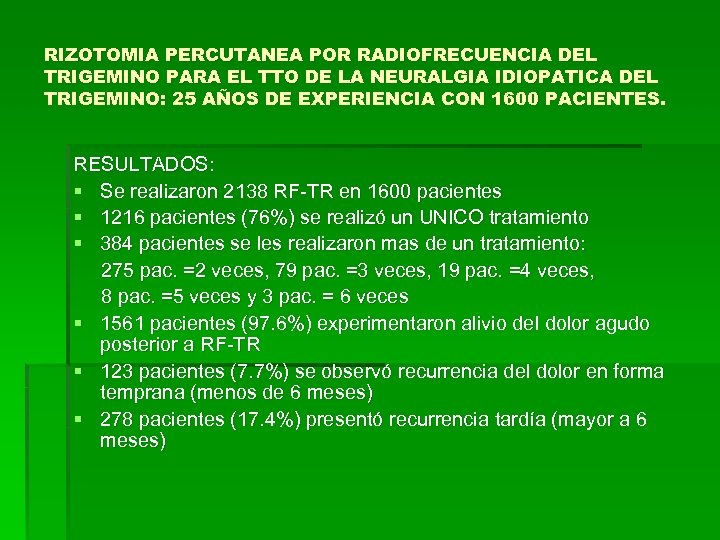

RIZOTOMIA PERCUTANEA POR RADIOFRECUENCIA DEL TRIGEMINO PARA EL TTO DE LA NEURALGIA IDIOPATICA DEL TRIGEMINO: 25 AÑOS DE EXPERIENCIA CON 1600 PACIENTES. RESULTADOS: § Se realizaron 2138 RF-TR en 1600 pacientes § 1216 pacientes (76%) se realizó un UNICO tratamiento § 384 pacientes se les realizaron mas de un tratamiento: 275 pac. =2 veces, 79 pac. =3 veces, 19 pac. =4 veces, 8 pac. =5 veces y 3 pac. = 6 veces § 1561 pacientes (97. 6%) experimentaron alivio del dolor agudo posterior a RF-TR § 123 pacientes (7. 7%) se observó recurrencia del dolor en forma temprana (menos de 6 meses) § 278 pacientes (17. 4%) presentó recurrencia tardía (mayor a 6 meses)

RIZOTOMIA PERCUTANEA POR RADIOFRECUENCIA DEL TRIGEMINO PARA EL TTO DE LA NEURALGIA IDIOPATICA DEL TRIGEMINO: 25 AÑOS DE EXPERIENCIA CON 1600 PACIENTES. RESULTADOS: § Se realizaron 2138 RF-TR en 1600 pacientes § 1216 pacientes (76%) se realizó un UNICO tratamiento § 384 pacientes se les realizaron mas de un tratamiento: 275 pac. =2 veces, 79 pac. =3 veces, 19 pac. =4 veces, 8 pac. =5 veces y 3 pac. = 6 veces § 1561 pacientes (97. 6%) experimentaron alivio del dolor agudo posterior a RF-TR § 123 pacientes (7. 7%) se observó recurrencia del dolor en forma temprana (menos de 6 meses) § 278 pacientes (17. 4%) presentó recurrencia tardía (mayor a 6 meses)